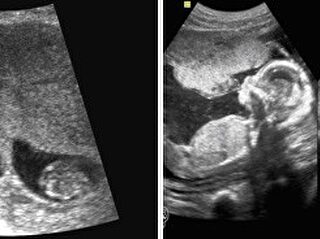

Para que haya un parecido físico real entre dos individuos, su similitud genética debe ser igual o superior al 80%. Los hermanos gemelos biológicos, que comparten padre y madre, tienen los mismos genes al 100%, pero su parecido físico no tiene que ser absoluto, pudiendo llegar a ser únicamente del 90%.

Esto se debe a dos factores genéticos que pueden variar: el epigenoma y la microbiota. El primero de ellos consiste en una red de compuestos químicos que rodean el ADN y modifican el genoma sin alterar los genes como tal. Por otro lado, la microbiota es un universo de microorganismos que conviven en nuestro interior. Estos dos factores pueden variar dependiendo del desarrollo de cada uno de los gemelos, causando que envejezcan de manera diferente a nivel de desarrollo físico.